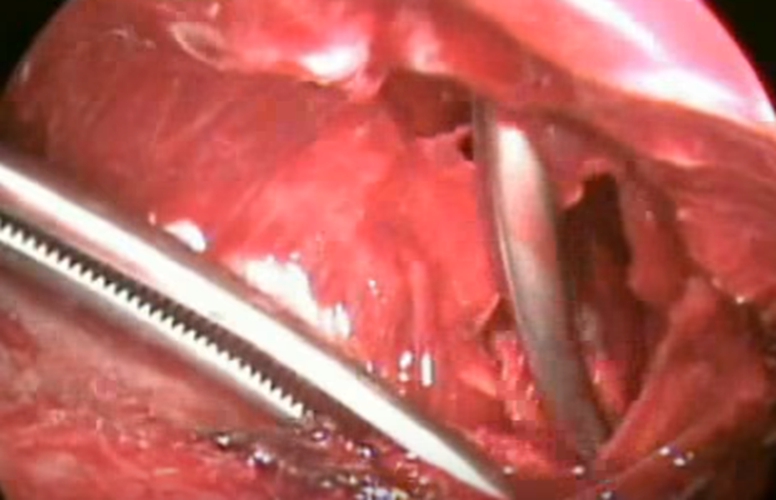

結核性胸膜炎胸腔鏡

結核性胸膜炎胸腔鏡的